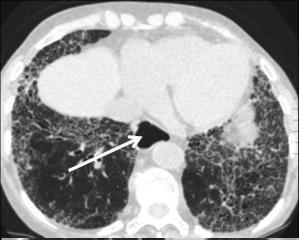

Images

radiologiques de la sclerodermie de oesophage en TDM

coupe axiale et coronal fenetre parenchymateus .Oesophage

en amont

et en aval de la region slerosante sont dilate

Image Achalasia de oesophage en

coupe TDM sagitale |

Meme cas en coupe TDM frontale ( coronale

) . |